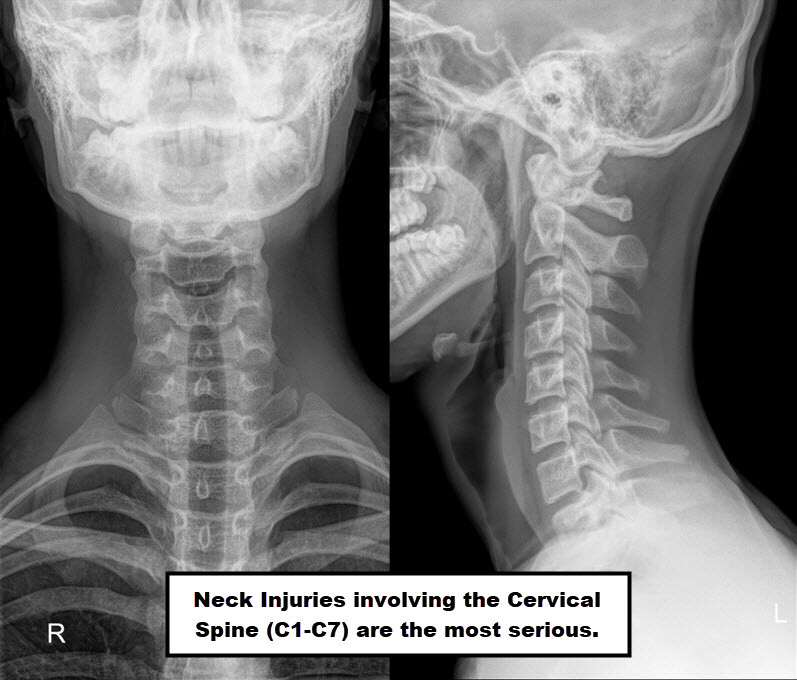

Common Neck Injuries In Sports . Web the most common athletic head injury is concussion, which may vary widely in severity. Web neck injuries are common incidents in sports. Playing sports can contribute to neck injuries of varying degrees of severity ranging. Web what are some of the common upper back and neck injuries experienced by many? A neck strain is a painful and debilitating injury. Web direct blows to your head or shoulder can lead to head injuries, as well as disc and nerve damage, strains and. The severity of neck injuries ranges from mild to severe. Web by terry zeigler, edd, atc. Last updated on august 12, 2024 by the sportsmd editors. Muscle sprain a muscle sprain. Injuries to the cervical spine can occur in all sports and range from soft tissue injuries to quadriplegia.

Common Neck Injuries In Sports Playing sports can contribute to neck injuries of varying degrees of severity ranging. A neck strain is a painful and debilitating injury. Playing sports can contribute to neck injuries of varying degrees of severity ranging. Web what are some of the common upper back and neck injuries experienced by many? Injuries to the cervical spine can occur in all sports and range from soft tissue injuries to quadriplegia. Web the most common athletic head injury is concussion, which may vary widely in severity. Web by terry zeigler, edd, atc. Web neck injuries are common incidents in sports. Muscle sprain a muscle sprain. The severity of neck injuries ranges from mild to severe. Last updated on august 12, 2024 by the sportsmd editors. Web direct blows to your head or shoulder can lead to head injuries, as well as disc and nerve damage, strains and.

Common Neck Injuries and Preventative Exercises JOI Rehab Common Neck Injuries In Sports Last updated on august 12, 2024 by the sportsmd editors. Web what are some of the common upper back and neck injuries experienced by many? Injuries to the cervical spine can occur in all sports and range from soft tissue injuries to quadriplegia. The severity of neck injuries ranges from mild to severe. Muscle sprain a muscle sprain. Playing sports. Common Neck Injuries In Sports.